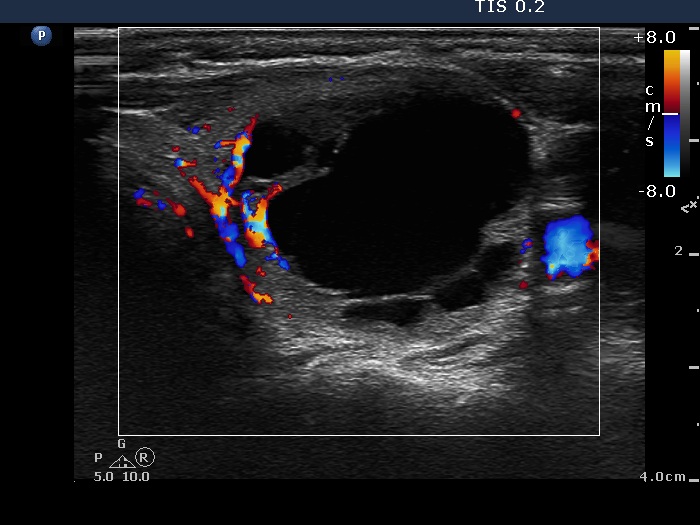

Clinical presentation: A 55-year-old woman was referred for aspiration cytology. She has a right lobectomy 10 years ago. At that time, a relatively small cystic nodule was already in the left lobe which was not operated. She noticed a lump in the left thyroid several weeks before the present examination.

Ultrasonography. There was no parenchyma in the right the thyroid bed. The left lobe was minimally hypoechogenic and had a large, multichambered cystic nodule. There were both hyperechogenic lines and granules within the dorsal wall of the cystic areas. The solid part was moderately hypoechogenic.

8 mL serous fluid was removed, thereafter the solid part was aspirated. Cytology resulted in benign cystic lesion.

Comment. Most of the hyperechogenic figures correspond to posterior back wall enhancement. There were a few colloid crystals within the cystic fluid.